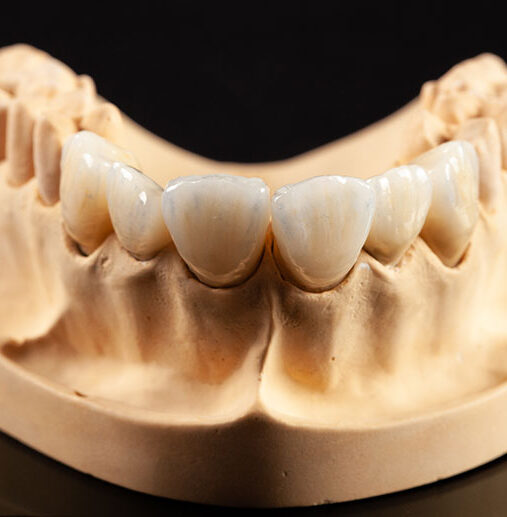

Sabit Protezler

Sabit Protezler Dişlerin mevcut sağlıklı dokularının korunması, diş eksikliklerinin giderilmesi, komşu dişlerin birbirlerine